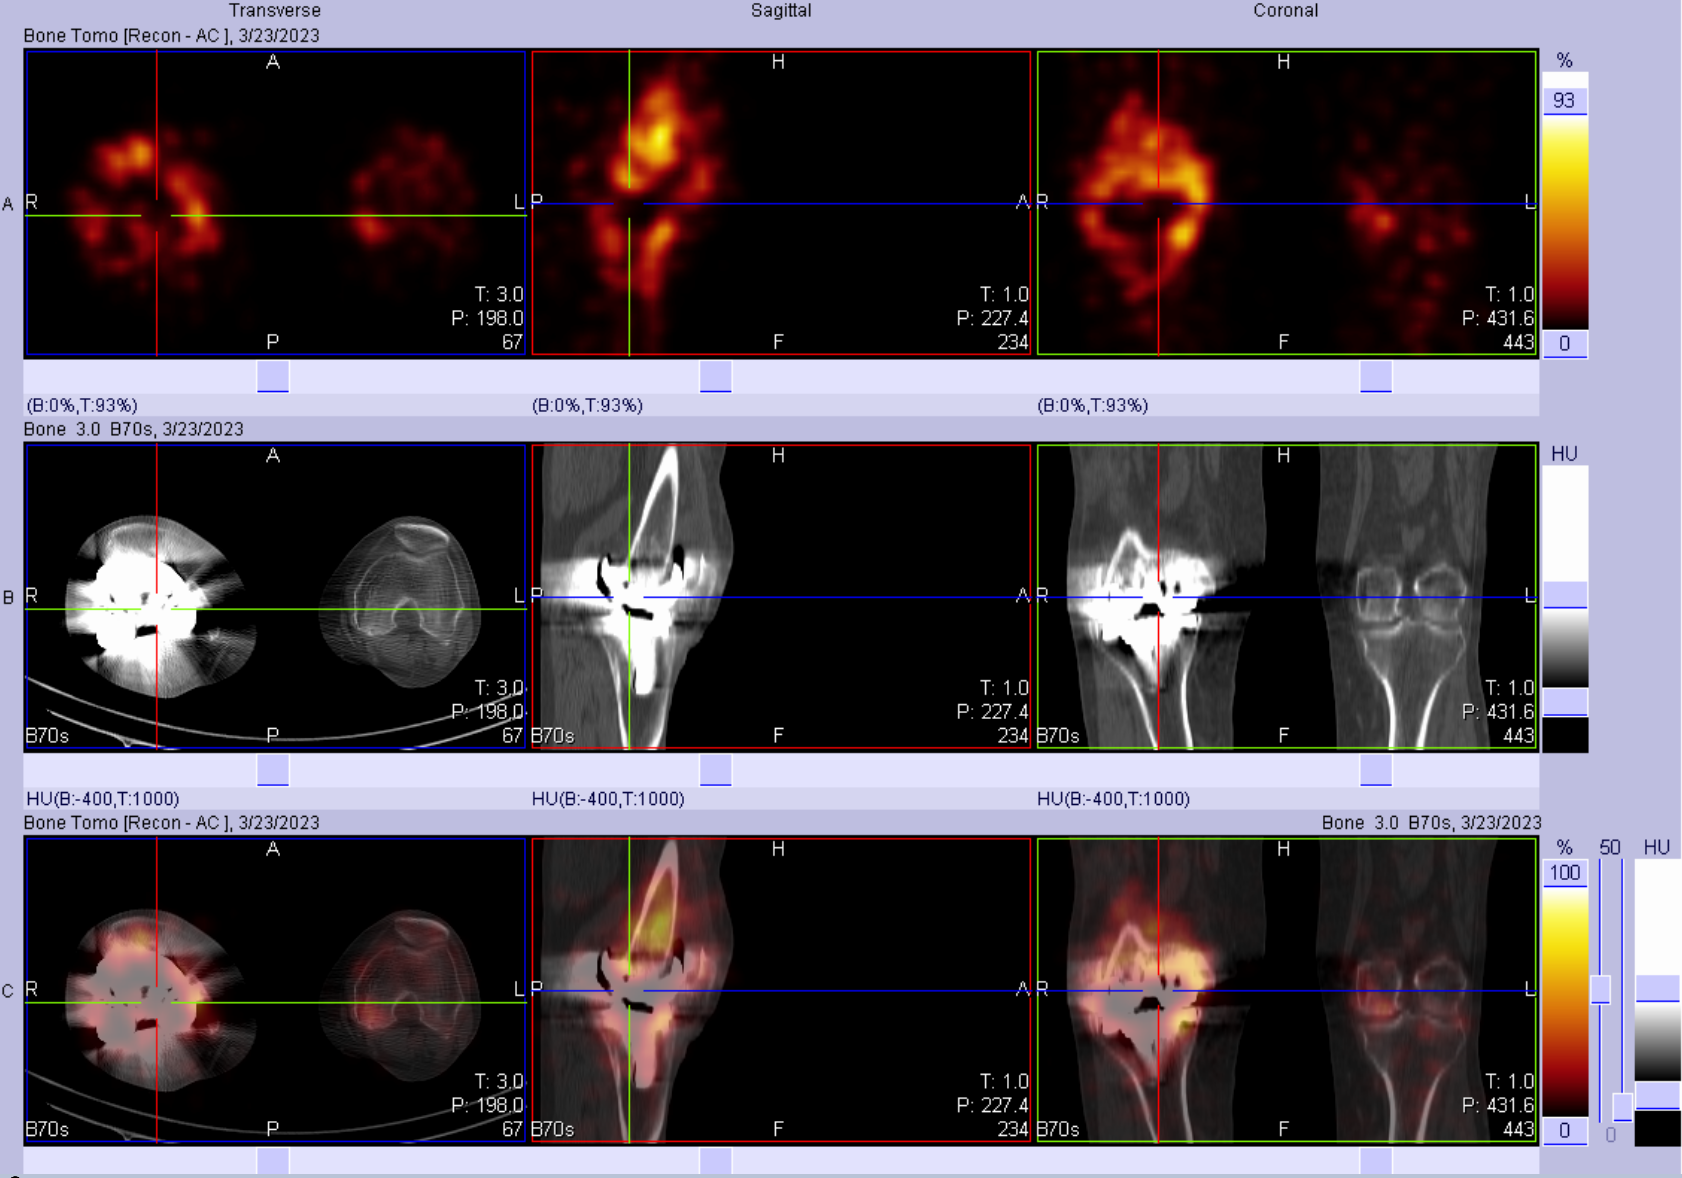

女性患者,8年前因“右侧膝关节炎”于我院行“右侧膝关节双间室置换”手术治疗,1年前无明显诱因出现右侧膝关节不适,自行口服止痛药物,不缓解。入院后完善相关化验检查,血常规:中性粒细胞计数7.69↑*10^9/L、C反应蛋白未见明显异常、血沉:37.0↑mm。

三相骨显像结果提示:右膝关节置换术后,三相骨显像血流相、血池相及延迟相阳性,结合影像特征考虑假体松动合并感染。

患者后续行手术治疗,术中见关节腔内脓液形成,膝关节假体松动。

①假体周围感染:典型表现为血流相、血池相、延迟相显像剂明显异常浓聚、范围广且弥漫,同机CT常可见软组织影、骨质破坏等影像。

②假体松动:典型表现为血流相、血池相在着力点附近出现放射性高摄取,延迟相可见假体两端局限性放射性浓聚,同机CT常可见骨吸收、骨质疏松等表现。